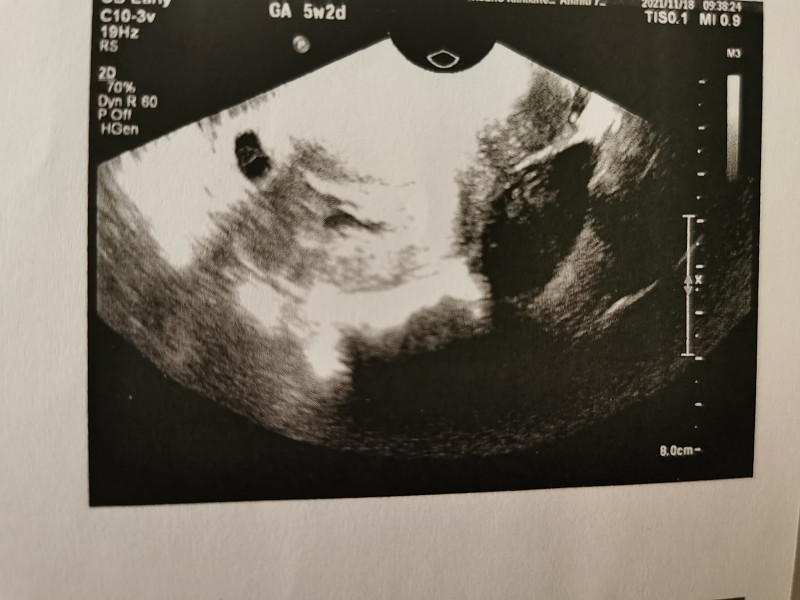

Labas merginos, gal galite pasidalinti savo nuomonėmis ir patirtimis? Esu 6sav+3 nėščia, visą šį laiką neturėjau jokių nusiskundimų, tačiau šiandien nuėjus i tualet…